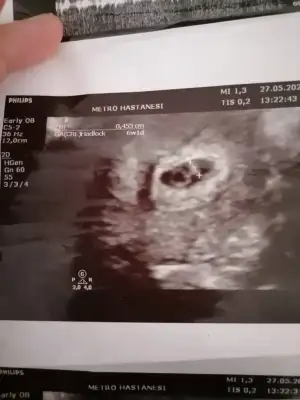

benimkini de görmediniz sanırım.6+2 karından ultrasonmerhaba.bi tahminde benim için bulunabilirmisiniz acaba :)

bu olur mu?6+2 karındanfotoğrafı yakınlaştırmadan çekip atabilir misiniz

paşa gibibu olur mu?6+2 karından